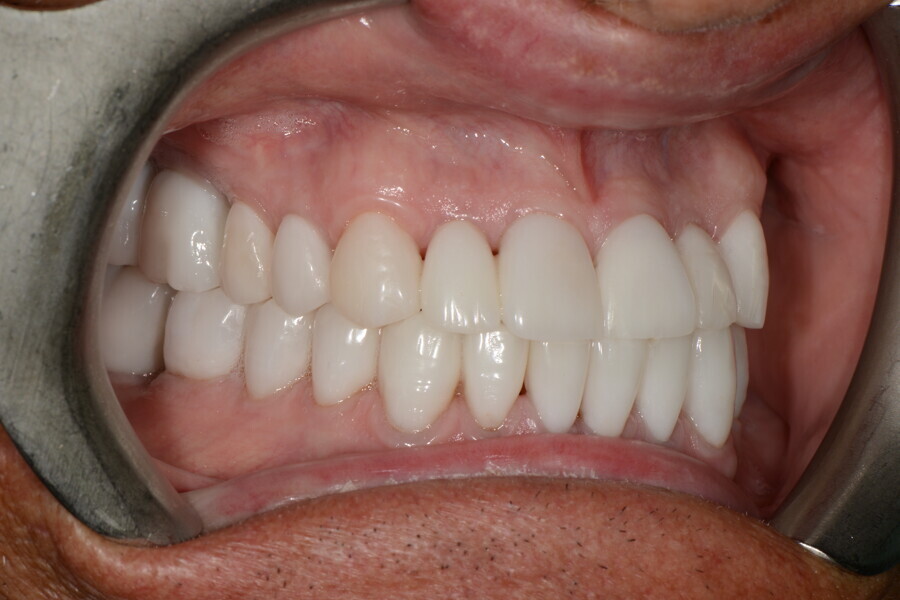

After the first phase of aligner treatment, we had achieved better inter-arch coherence, better maxillary arch expansion, and some space for improving the anterior tooth proportions restoratively (Fig. 19). We then temporarily restored the anterior teeth directly with composite, closing the spaces, improving the tooth proportions and further increasing the maxillary arch expansion (Fig. 20). We used restorative arch expansion to reduce the orthodontic destabilisation of the teeth to achieve the correct inter-arch coherence and retain the teeth in the cortical bone.38 A refinement aligner phase was undertaken to improve the final alignment of the gingival zenith and to improve the inter-arch coherence (Fig. 21). The periods of the first orthodontic phase and of the refinement were used to augment the mandibular and maxillary bone and to place the implants (Fig. 22). At the end of the orthodontic treatment, the case was finalised with ceramic veneers in the anterior area and temporary restorations on the implants in the posterior area (Figs. 23–26).

The provisional phase of about four months was important to allow the peri-implant tissue to mature and to teach the patient to chew correctly with chewing gum, cotton rolls and silicone masticatory sticks. This is fundamental training for the patient to achieve the correct alternating unilateral masticatory cycle needed to obtain the ideal rehabilitation of the masticatory system. We wanted the patient to achieve ideal masticatory and swallowing function. After sufficient rehabilitation time, we finalised the case with posterior zirconia crowns screwed on to the implants (Fig. 27).26

Our ideal final rehabilitation goals were:

• posterior stability;

• inter-arch coherence and U-shaped arches;

• anterior freedom during mastication;

• minimum disclusion vertical dimension;

• alternating unilateral masticatory cycle;

• physiological swallowing and high tongue posture against the palate; and

• mandibular disclusion advancing the mandible freely.

For maintenance purposes, after prosthetic finalisation, the patient was to carry on with the Froggymouth therapy and to use the Ri.P.A.Ra. for physiotherapeutic exercises and mastication training (Fig. 28). It was strongly recommended that the patient wear a mandibular occlusal splint during sleep. This occlusal splint was designed with disclusion guides to advance the mandible and ensure balanced contralateral support (Fig. 29).11, 39 We achieved an aesthetic appearance with adequate inter-arch coherence and a better cephalometric result (Figs. 30 & 31).